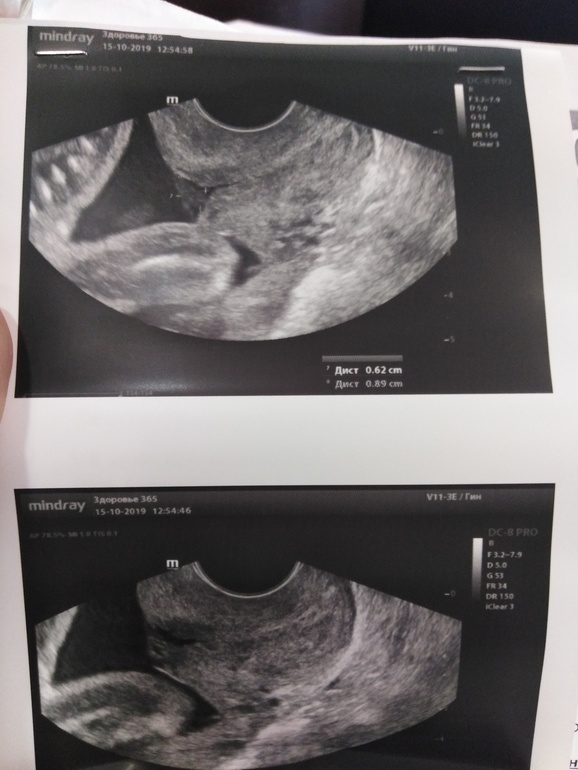

Итог: поперечное предлежание, пиелэктозия так ещё и есть...

Самое интересное: шейка 42, но внутренний зев воронкообразный.... 🙈 🙈 🙈 Это вообще как? 🤔 Узист сказала идти к геникологу....

Позвонила на участок, получила звиздюлей, что пошла на узи, а не на приём.... Не приятно.... А Больше всего офигела от фразы: вам в узи ДИАГНОЗ написали? 🤔 Вот я тупая? Как узист может ДИАГНОЗЫ ПИСАТЬ? Она вроде исследование проводит, а диагнозы врач пишет, нет? 🤔 🤔 🤔 Написала: шейка 42мм,вн.зев воронкообразный.... И фотки дала....

Глубина воронки 0,62см, ширина в самом широком месте 4,23см....🙈